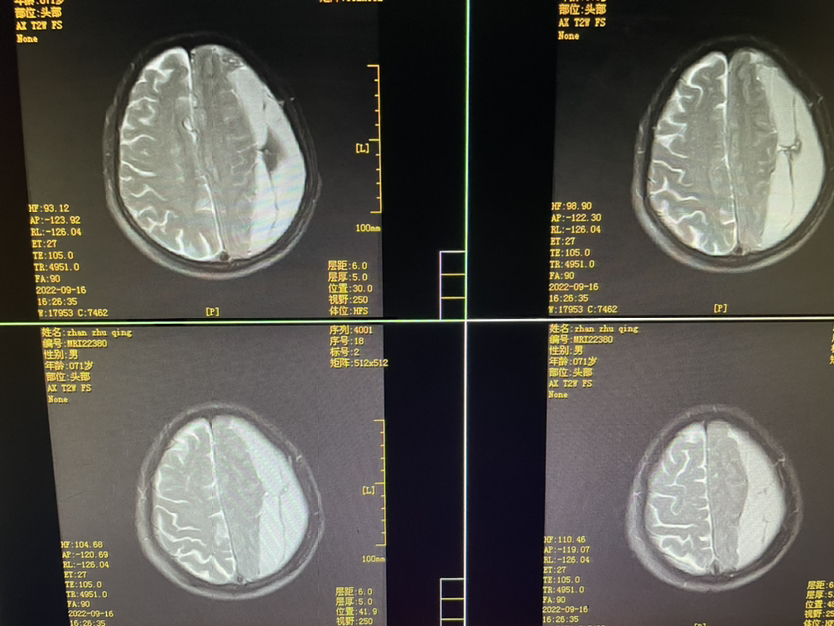

448859,头疼四肢乏力4天,71y